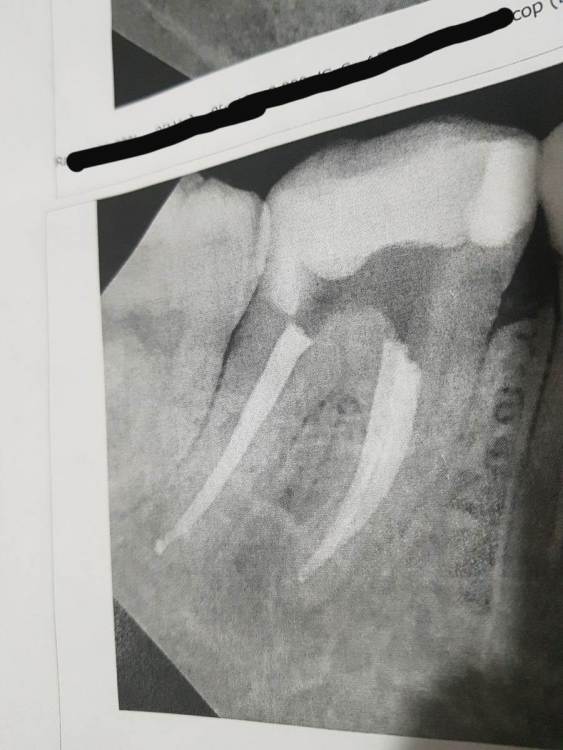

Александра117 Опубликовано 19 мая, 2022 Поделиться Опубликовано 19 мая, 2022 (изменено) Здравствуйте, Мне 15 дней назад провели удаление нерва и пломбирование каналов нижней 7ки под микроскопом. Сейчас стоит временная пломба. Я должна буду через несколько дней прийти еще раз в Эту Стоматологию, чтобы поставить постоянную пломбу. Каждого визита приходится ждать около 3х недель, потому что большая запись, хоть и платная и очень дорогая стоматология. После пломбировки каналов сделали контрольный снимок. На снимке видно, что за пределы корня вышел материал. Врач сказал, что это не страшно. Каналы пломбировались гуттаперчей. Но то, что вышло за верхушку это не гуттаперча, а какая то паста. Название не знаю, но врач сказал, что она биосовместима и рассосется сама за Два Года. Это все со слов Стоматолога. Прошло 16 дней после пломбировки каналов. В общем целом зуб чувствует себя нормально. Но болит, если жевать этой стороной. Лечение проводил опытный Врач под микроскопом. Скажите, много ли материала Вышло за верхушку? Нужно ли теперь этот канал перелечивать? Или это не критично? Рассосется ли то, что вышло за корень? И как вообще Вы оцениваете эту работу Стоматолога? Прилагаю снимки до и после лечения. Изменено 19 мая, 2022 пользователем Александра117 Ссылка на комментарий

Бардо Опубликовано 20 мая, 2022 Поделиться Опубликовано 20 мая, 2022 Судя по снимку очень аккуратная и качественная работа, вы напрасно переживаете. После эндодонтического лечения могут быть боли аналогичные вашим, о чем вас доктор наверняка предупредил и это нормально. Вышедший материал, тем более в таких микроскопических количествах не несёт и не может нанести никаких угроз 3 1 Ссылка на комментарий

red_butler Опубликовано 22 мая, 2022 Поделиться Опубликовано 22 мая, 2022 у Вас хороший доктор, каналы отлично пролечены 2 Ссылка на комментарий

Гарриевич Опубликовано 22 мая, 2022 Поделиться Опубликовано 22 мая, 2022 Работа хорошая, это даже не считается выходом материала. У меня к вам вопрос: откуда появилось недоверие к доктору? PS ко мне ждать записи иногда приходится 5-6 недель)) 2 Ссылка на комментарий

Carioznik Опубликовано 29 мая, 2022 Поделиться Опубликовано 29 мая, 2022 28.05.2022 в 04:42, Александра117 сказал: материал вышел за пределы корня У Вас грамотный доктор, некоторые бы сказали: "идеально! все чётко до верхушки, ничего не вышло". Но то, что вышло в одном из 3 каналов - это такие микроскопические количества, которые ни на что не влияют. Вот, взгляните, когда действительно много вышло (но даже при таких количествах, прогноз, в большинстве случаев, будет благоприятный): 2 Ссылка на комментарий